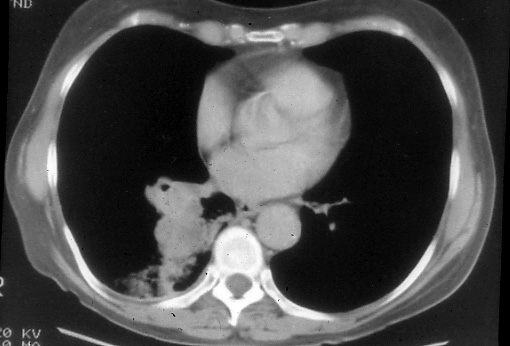

LUNG

CANCER

A Handbook for Staging, Imaging, and Lymph Node Classification